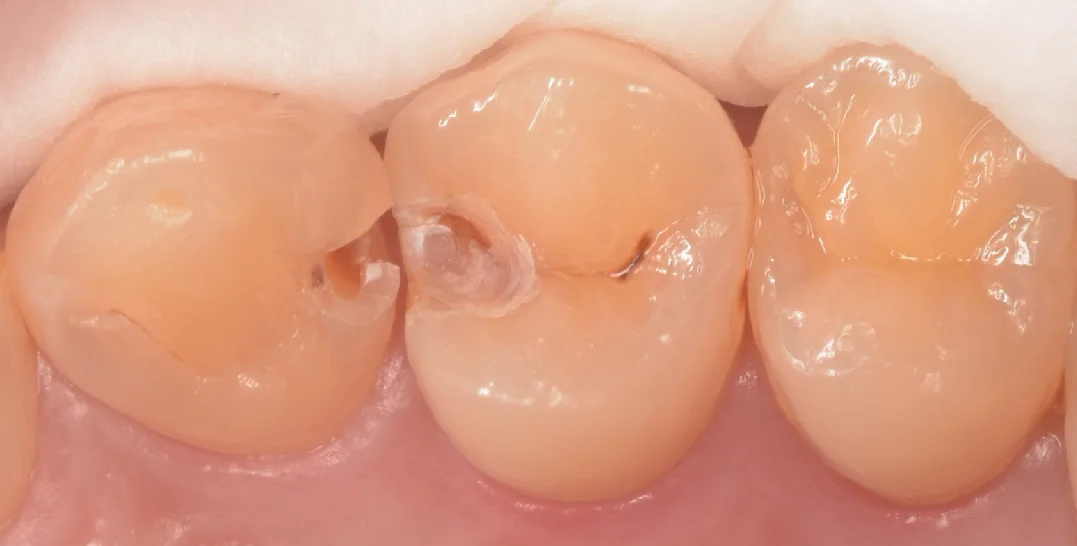

軽く削ってみたのがこちらの写真です。

中央の歯のプラスチックはまだ取り切れてはいないですが、すでに虫歯が露出していますね。

左側の歯は表面のエナメル質がほぼ消失して、大きな穴が空いていたのがわかります。

この方はここのところに食べかすが挟まる+フロスが引っかかるとのことでむし歯になっていると言う予測の元、いろいろな医院さんを探して当院を選ばれました。